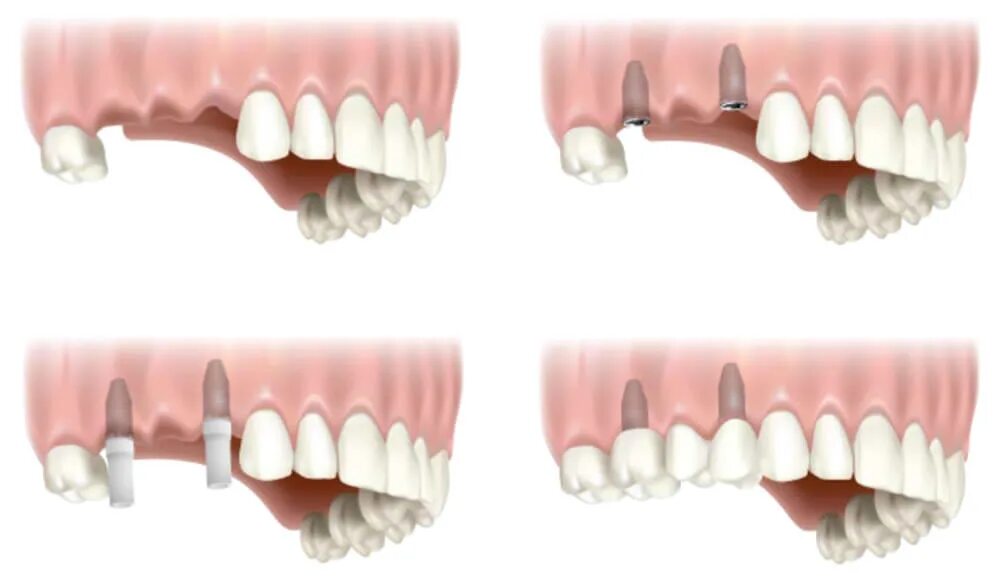

Поставить 4 зуба